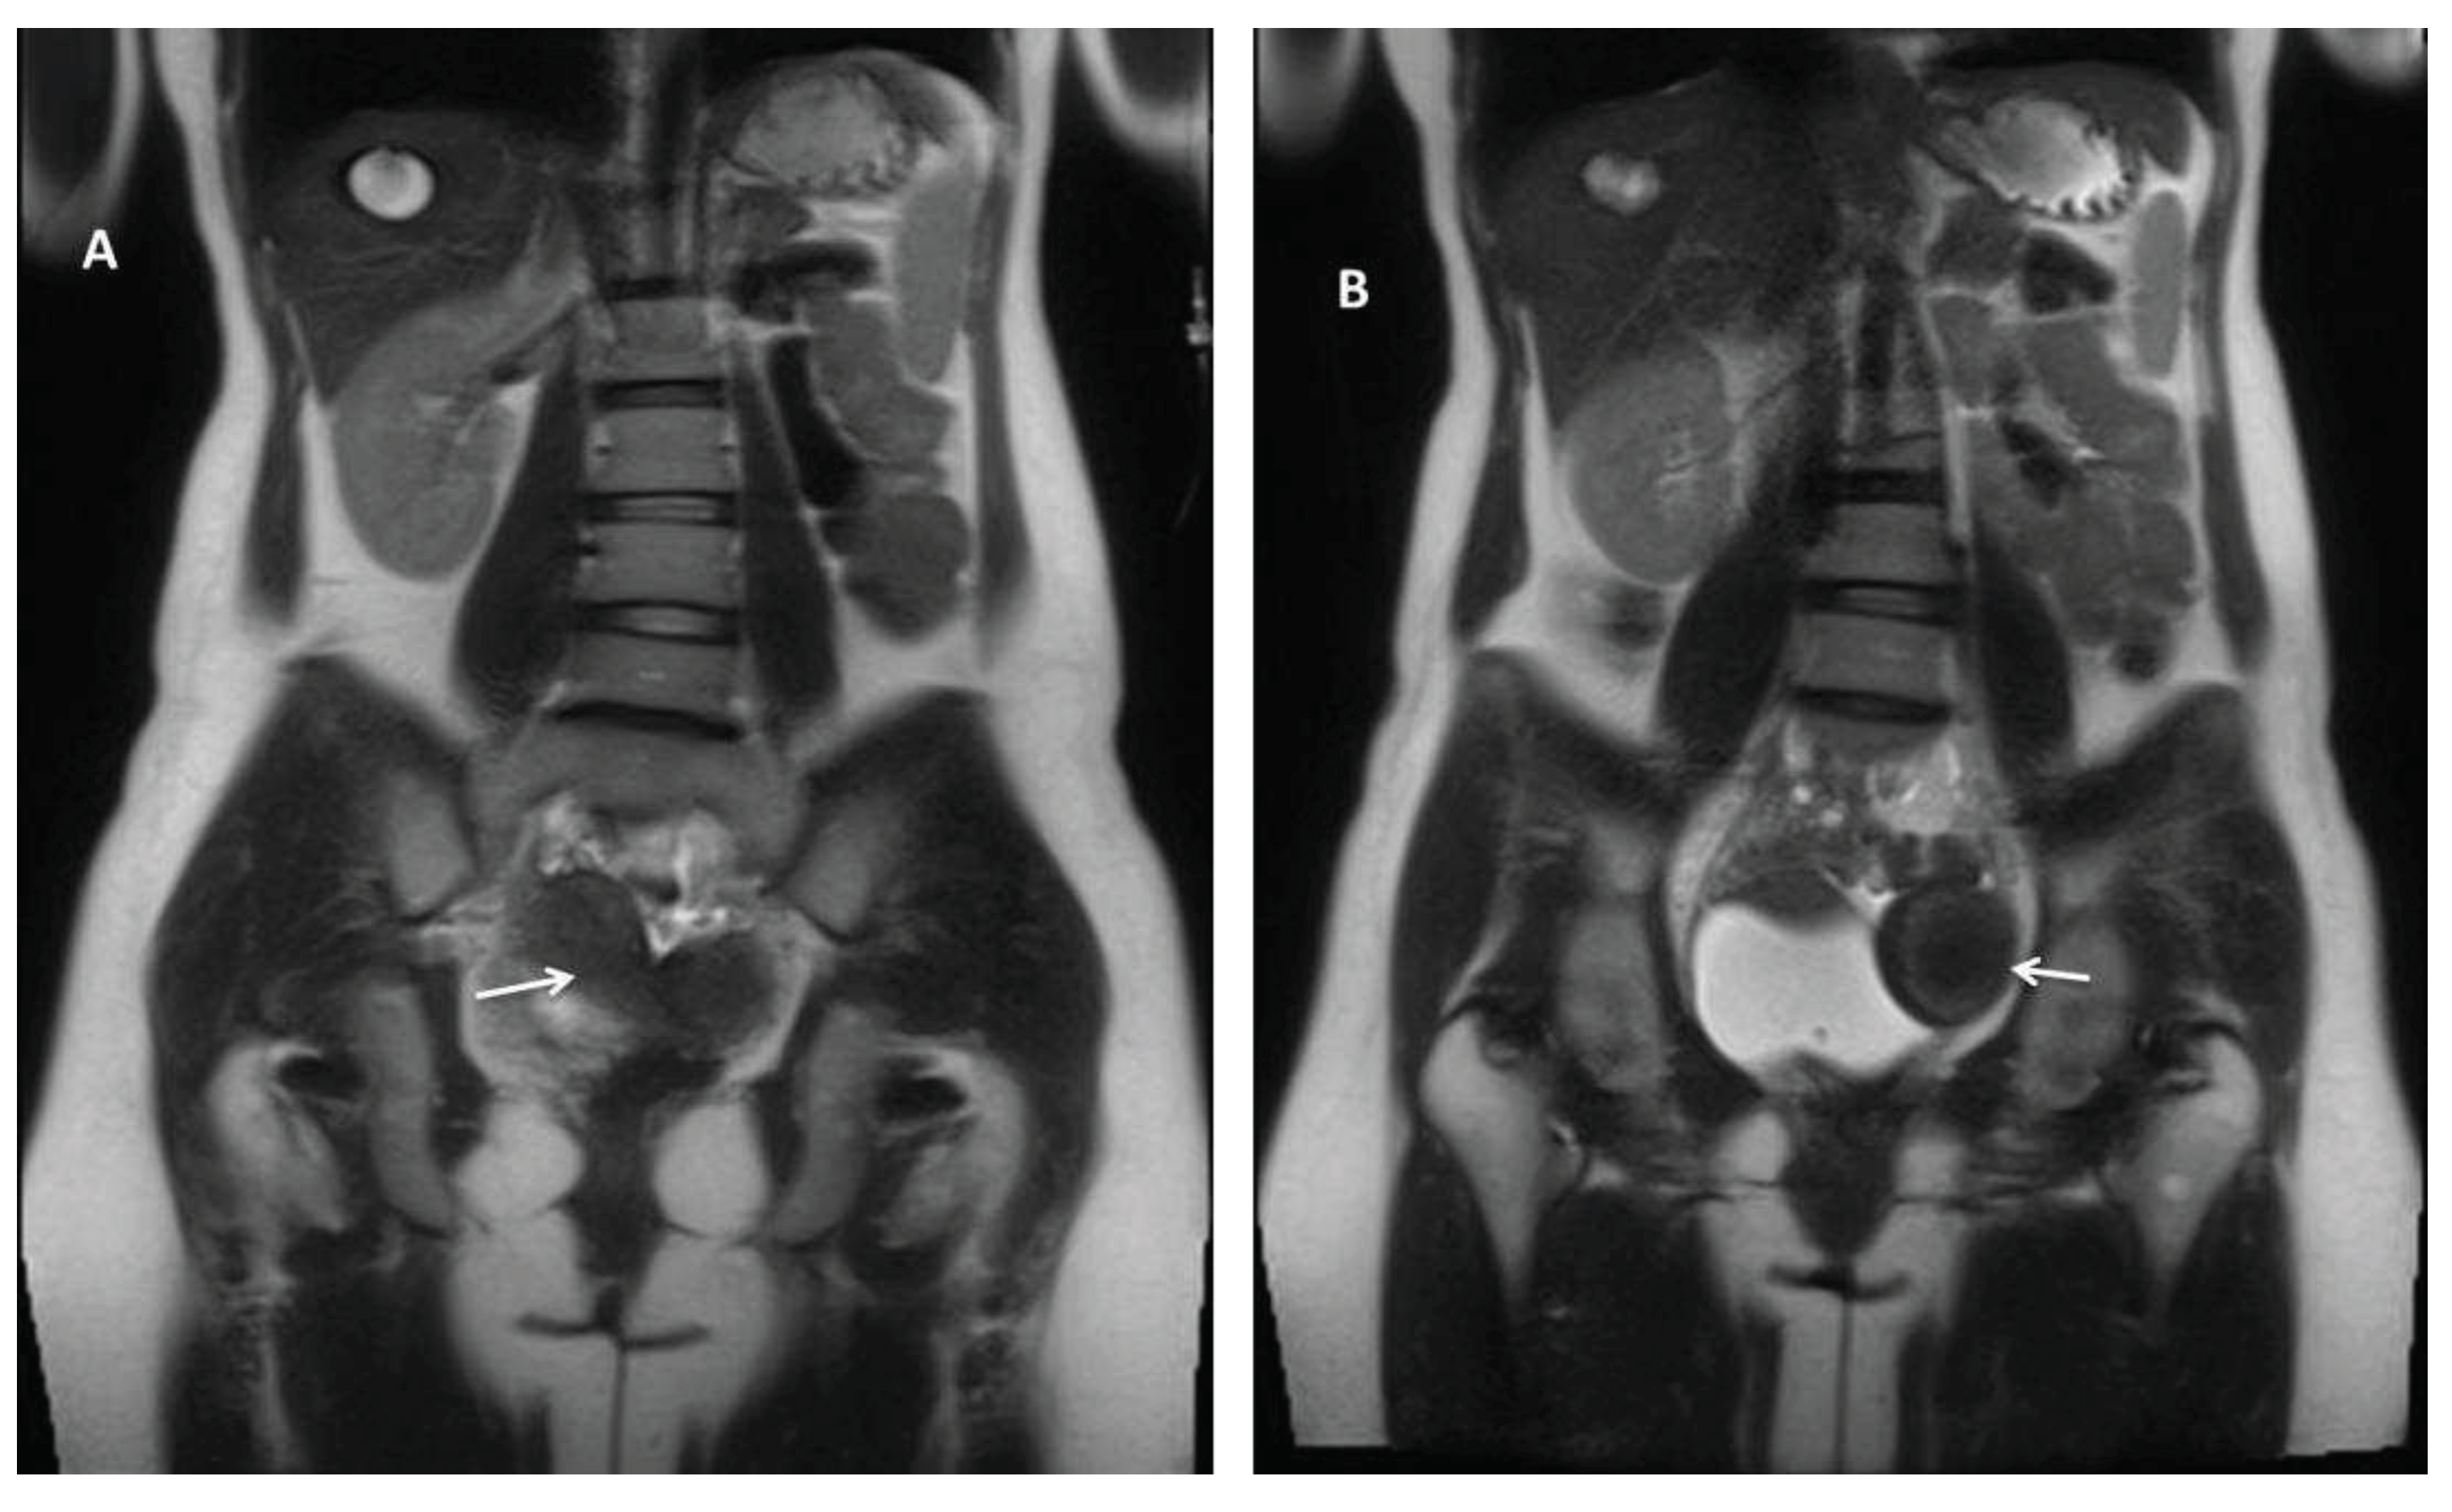

Figure 2. Abdominal and pelvic MRI, coronal T2-weighted images. Pelvic magnetic resonance imaging (MRI) revealed: A) a normally looking right uterus (white arrow) and right ovary and B) a pelvic mass located mainly to the left (white arrow), measuring 47/63 mm, with similar enhancement to the uterus, advocating a Müllerian duct anomaly (MDA) type U4aC0V0 with large hematometra and solitary right kidney and absent left kidney.